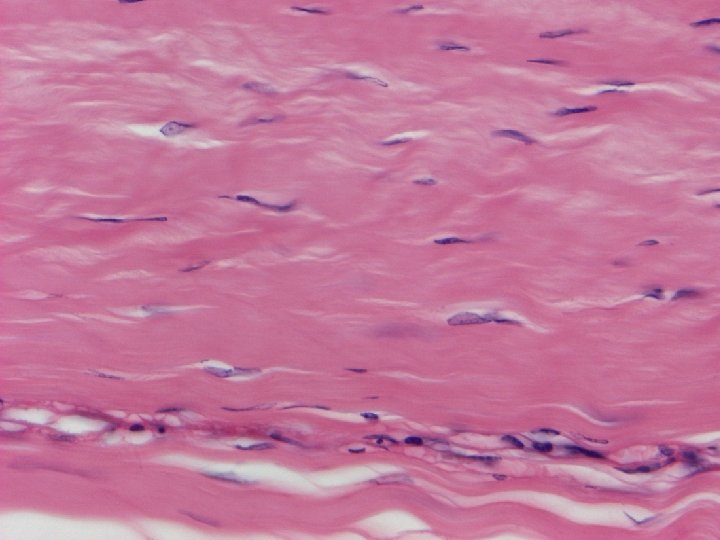

fibrous cartilage